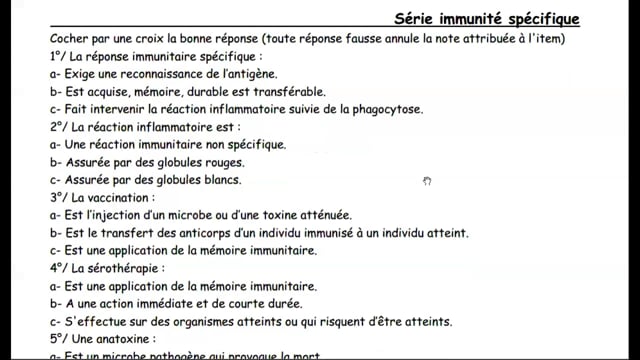

Sciences SVT